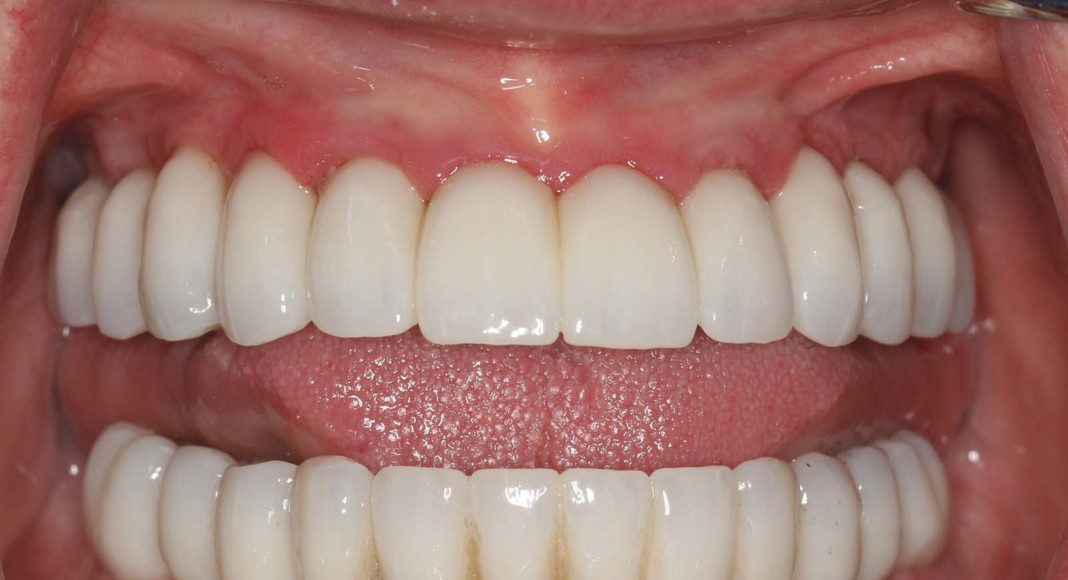

We are now ready to begin the fabrication process of the definitive, zirconia bridges. These are the wax protypes that we use to determine tooth length, width, proper bite (lip retracted). The patient and their family members are invited to this appointment so that everyone can view the over aesthetics before we process in zirconia. Once it’s in zirconia, we cannot make big changes.

Occlusal view of the upper arch. Note: The tissues are a little red. Many patients, especially women have a slight allergy to the acrylic of the temporary bridges. This resolves after the zirconia bridge is placed.

Occlusal view of the lower arch. Note: The tissues are a little red. Many patients, especially women have a slight allergy to the acrylic of the temporary bridges. This resolves after the zirconia bridge is placed.

Occlusal view, upper, day of delivery. If you look closely, you can see the final prosthetic screw (blue). This channel is covered with composite resin.